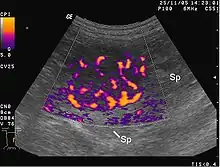

Image écho-Doppler montrant l'hypervascularisation

L’angiogenèse tumorale est la prolifération d'un réseau des vaisseaux sanguins qui pénètrent dans les croissances cancéreuses, fournissant des substances nutritives et de l'oxygène et enlevant les déchets : le chercheur Judah Folkman montre en 1971 que la tumeur ne peut grossir sans angiogenèse au-delà de mm3[4]. La tumeur angiogénétique commence en réalité lorsque des cellules de tumeur cancéreuses laissent échapper des molécules qui envoient des signaux au tissu hôte normal qui l’entoure. Cette signalisation active certains gènes dans le tissu hôte, lequel, à son tour, permet aux protéines de susciter la croissance de nouveaux vaisseaux sanguins.